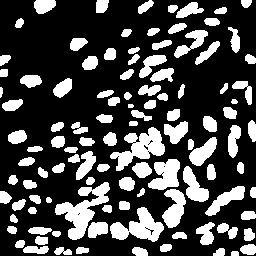

To better retain the deep features of an image and solve the sparsity problem of the end-to-end segmentation model, we propose a new deep convolutional network model for medical image pixel segmentation, called MC-Net. The core of this network model consists of four parts, namely, an encoder network, a multiple max-pooling integration module, a cross multiscale deconvolution decoder network and a pixel-level classification layer. In the network structure of the encoder, we use multiscale convolution instead of the traditional single-channel convolution. The multiple max-pooling integration module first integrates the output features of each submodule of the encoder network and reduces the number of parameters by convolution using a kernel size of 1. At the same time, each max-pooling layer (the pooling size of each layer is different) is spliced after each convolution to achieve the translation invariance of the feature maps of each submodule. We use the output feature maps from the multiple max-pooling integration module as the input of the decoder network; the multiscale convolution of each submodule in the decoder network is cross-fused with the feature maps generated by the corresponding multiscale convolution in the encoder network. Using the above feature map processing methods solves the sparsity problem after the max-pooling layer-generating matrix and enhances the robustness of the classification. We compare our proposed model with the well-known Fully Convolutional Networks for Semantic Segmentation (FCNs), DecovNet, PSPNet, U-net, SgeNet and other state-of-the-art segmentation networks such as HyperDenseNet, MS-Dual, Espnetv2, Denseaspp using one binary Kaggle 2018 data science bowl dataset and two multiclass dataset and obtain encouraging experimental results.